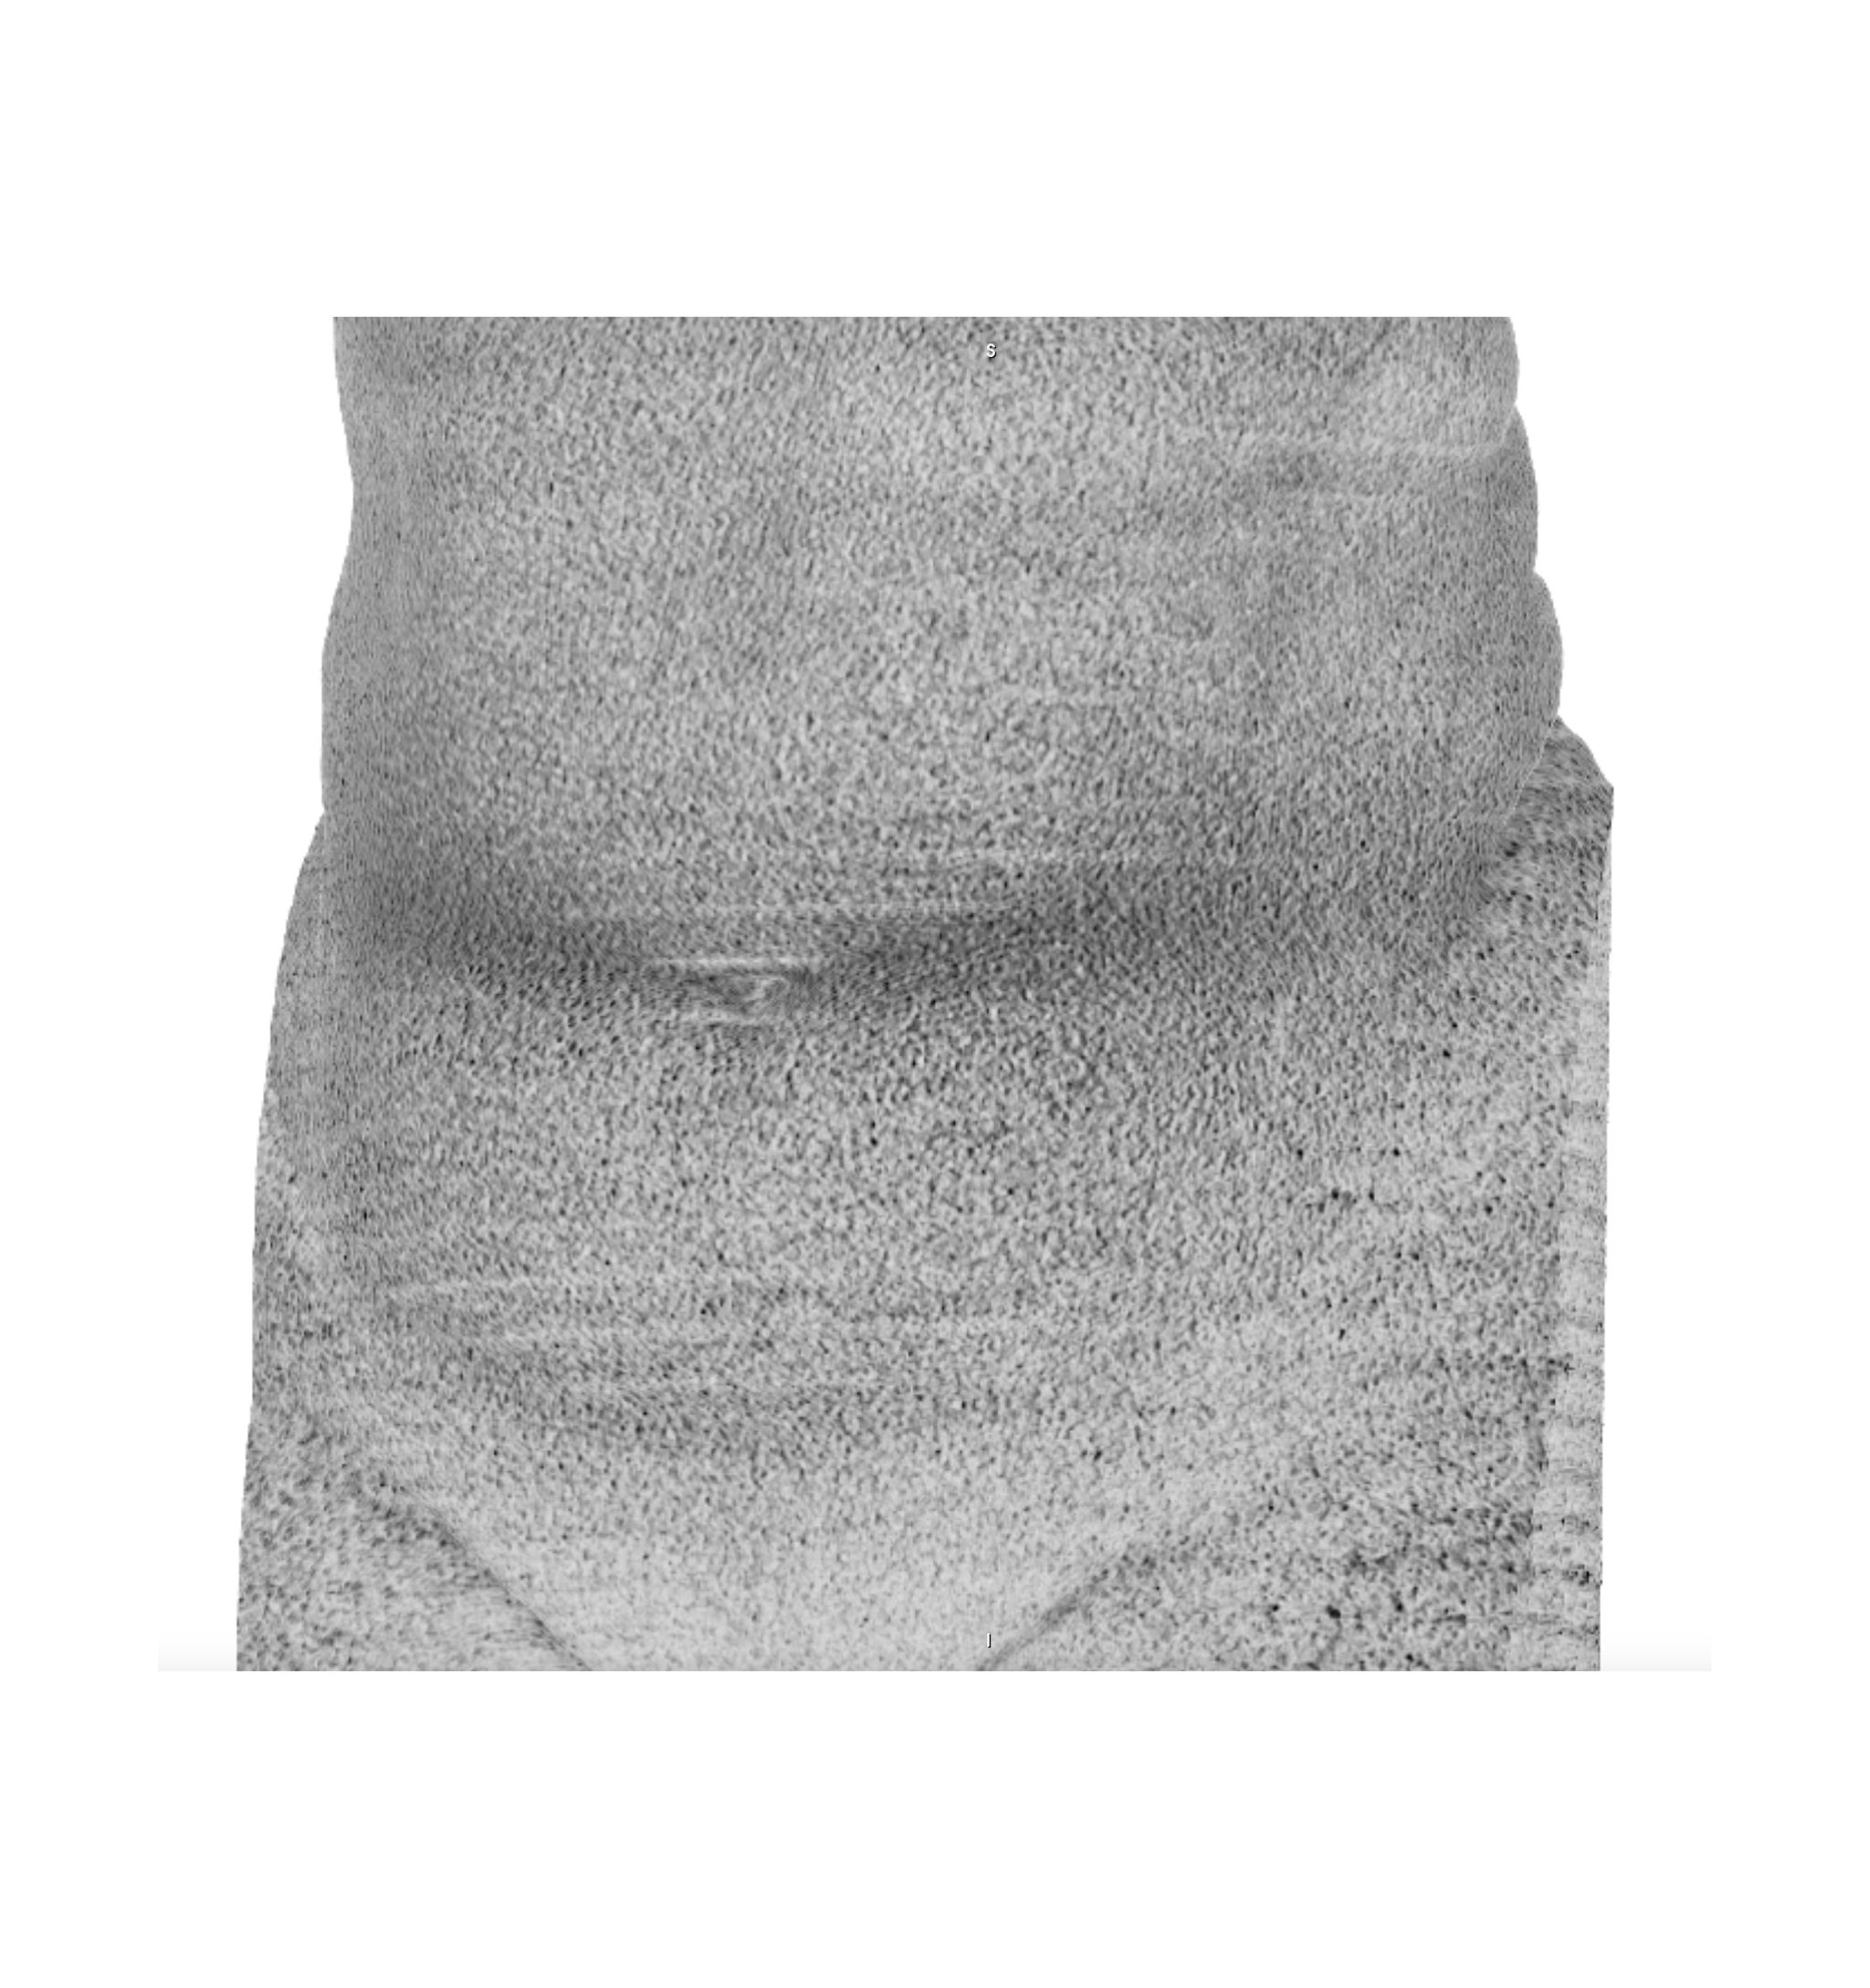

Chasing Intensities considers the body through its relationship to contemporary medical imaging technologies.

In this project, I look at the visual limit between the inside and the outside, the inner and the outer. I combine different visual approaches to materialise the body, using medical imagery, photography from manuals and radiology software. Decontextualised from their origin, these images speak of medicine’s relationship to both sex and violence, and remind us that, in medicine, to go into the body is always to go into the image first.